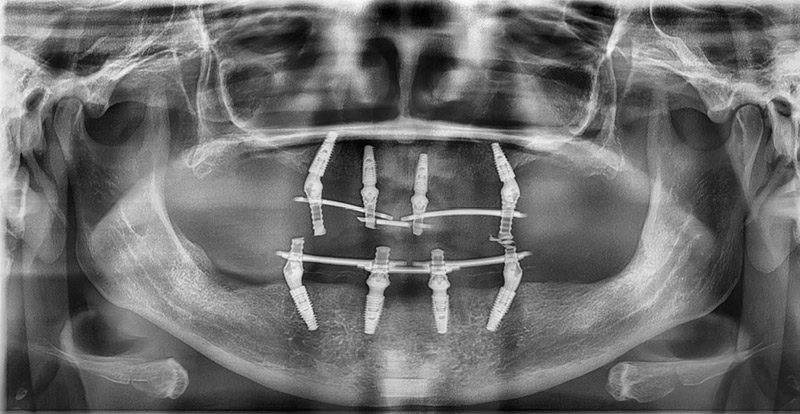

Вот так на снимке выглядят импланты, на которых установлены протезы